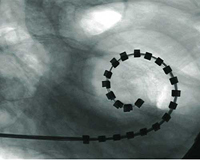

La hipoacusia neurosensorial es debida a una alteración del oído interno, ya sea desde el nacimiento o de forma adquirida. En estos casos debemos recurrir a algún tipo de dispositivo electrónico como son los audífonos convencionales. Si los audífonos no son útiles, los pacientes pueden beneficiarse de dispositivos que requieren implantación quirúrgica como los implantes cocleares.